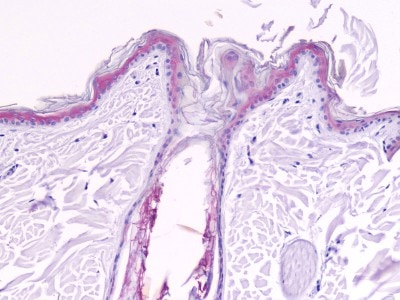

Photo 9 : Hyperkératose lamellaire massive, présence d’une nappe parakératosique compacte (HES, x100)

Photo 10 : Hyperkératose parakératosique compacte formant des spicules filiformes de kératine à la surface (HES, x200)

Les raclages sont négatifs. L’examen histopathologique révèle une considérable hyperkératose à kératine compacte, souvent parakératosique, s’enracinant profondément dans les follicules pileux, orthokératosique en d’autres endroits. Le derme est très légèrement inflammatoire. Il n’y a aucun élément figuré à la réaction au PAS. Ces lésions microscopiques sont compatibles avec une ichtyose, une dermatose améliorée par le Zinc .

L’examen histologique confime l’hyperkératose parakératosique en nappe, essentiellement infundibulaire. Les cellules parakératosiques sont arrondies et se détachent une par une, sans perdre leur forme.

On constate également une hyperplasie épidermique et une papillomatose, et l’absence de dégénérescence vacuolaire des kératinocytes basaux.